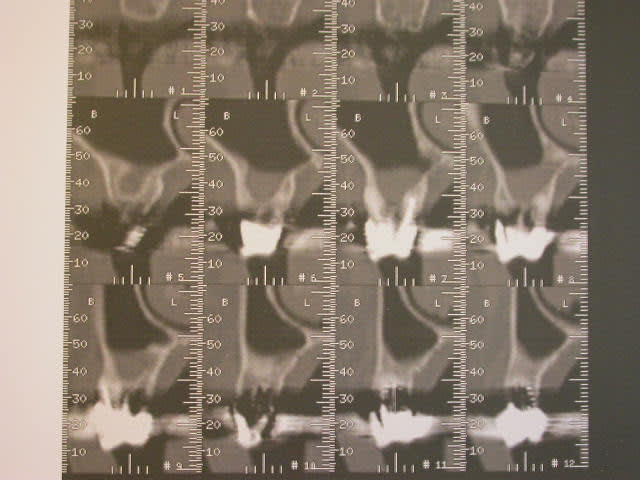

J’ai demandé un scan pour déceler une fracture de racine et y voir plus clair. Je mets les photos du scan. Je le trouve inexploitable, le radiologue me confirme que les clichés sont inexploitables, que c’est du à la présence de métal dans les couronnes des secteurs postérieurs et qu’on n’aura pas de meilleurs résultats en recommençant ce scan.

- le scan, il me semble que la présence de métal n’interfère pas forcément et que l’on pourrait obtenir des clichés plus nets ou plus lisibles, votre avis ??

Deuxième chose, le scan n'est pas si pourri que ça, par contre tes clichés photos oui, t'as du parkinson qui te guette.

Troisième chose, le scan semble pas montrer grand chose à première vue sauf une atteinte de furcation ou placher de la 16 avec un foyer là dessous => probable à extraire, à explorer

En toute logique, et surtout dans ces cas spéciaux, il ne faut pas faire un dentascan, et ça le radiologue aurait du y penser, cette grosse banane, mais il faut faire un scan crâne complet pour avoir tous les sinus.

Du coup l'ORL va demander un scan complet de la face et 2e irradiation => radioprotection quand tu nous tiens.

Apres a un niveu locale je vois un apex extracortical qui peut etre souvent a l origine de douleurs, pas de plancher inter radiculaire sur 16 avec reaction inf du sinus attenant.